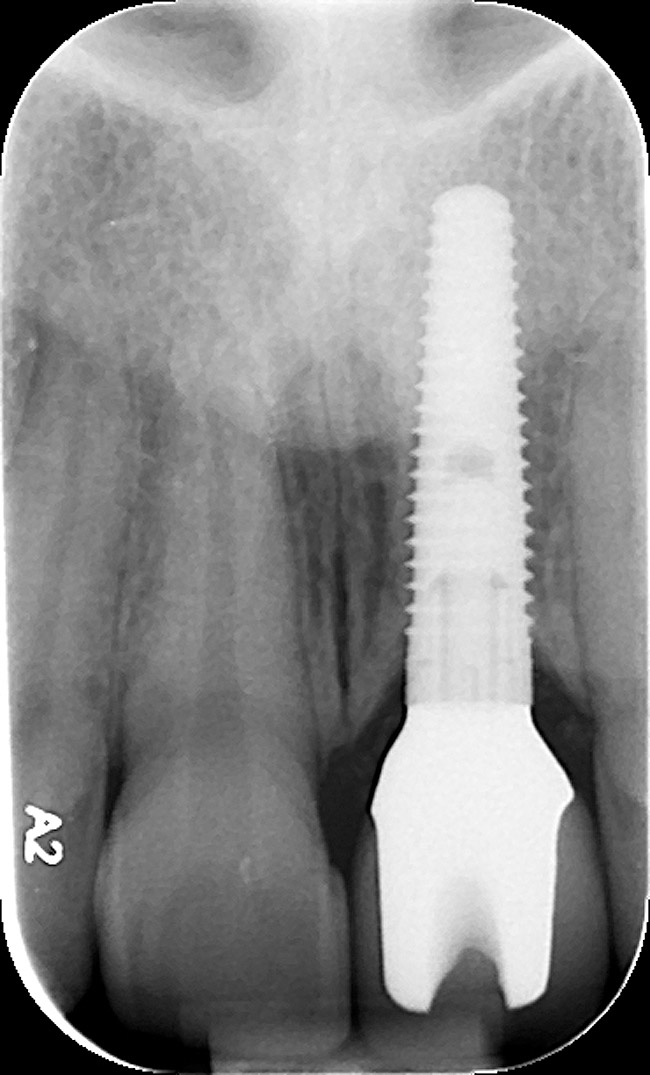

The periodontist positioned a 4.3-mm x 16-mm regular-platform implant flush with the facial crest and 1 mm subcrestally interproximally (Figure 15), with a manually driven final seating torque value > 50 Ncm, followed by hand-tightened attachment of the immediate temporary abutment.

Figure 15  Regular-platform 4.3-mm x 16-mm implant positioned in osteotomy—periapical view.

Figure 15